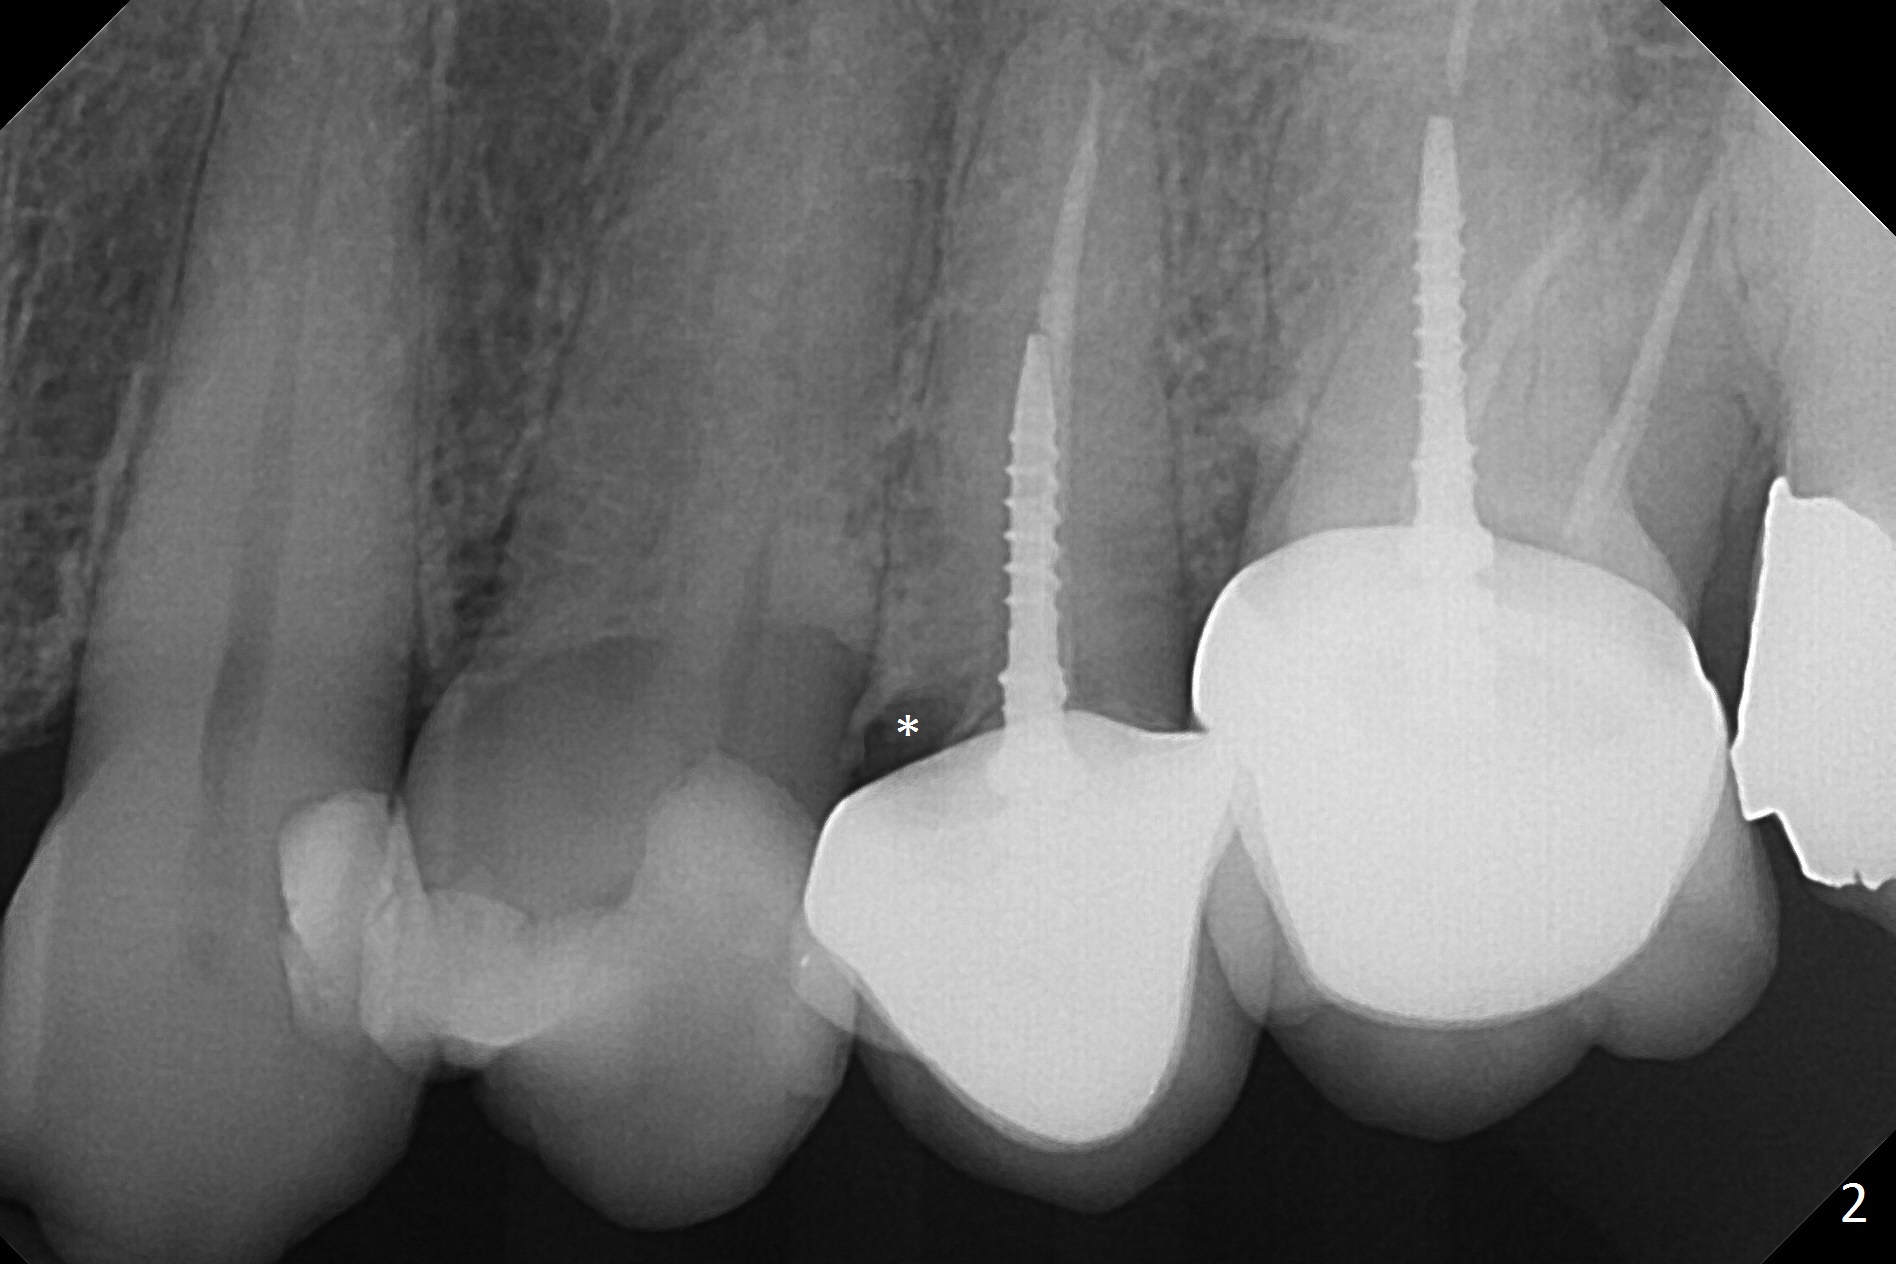

A 60-year-old woman returns to office with chief complaint "upper left crown is loose again".  Clinical exam confirms #13 crown fracture at the gingival level (Fig.1,2 *).  Since the native bone is short, an implant (Fig.3 green) should penetrate the sinus floor for primary stability.  To protect the sinus membrane, PRF membranes (purple curved line) will be inserted prior to bone graft (red circles) and the implant.  A pair abutment is expected to be 5x5 (5.7 exactly, blue) (Fig.3, pink) mm.  The implant should be placed palatally to avoid buccal metal show through.